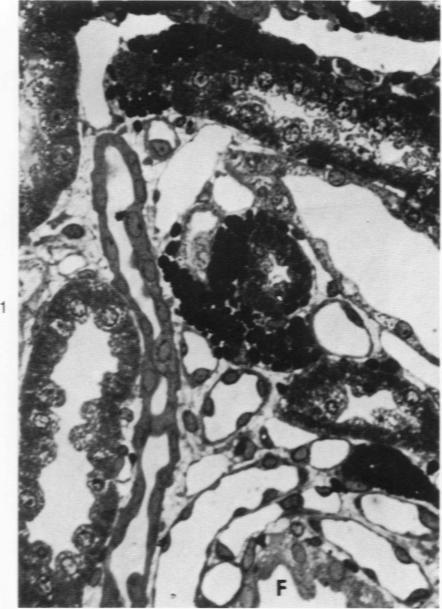

The pathogenesis of experimental unilateral hydronephrosis was studied in the rat, with emphasis on the role of medullary vascular obstruction. The medullary circulation was evaluated after increasing periods of ureteral obstruction (up to 48 hours) using in vivo perfusion of silicone rubber or colloidal carbon. Evidence of inner medullary hypoperfusion was seen after 1 hour, and by 6 hours, the entire papilla was ischemic. Papillar hypoperfusion was still present at 24 and 48 hours, but significant recirculation occurred in the presence of continued obstruction. Release of ureteral obstruction caused rapid reversal of the perfusion defect. Histologic studies of the renal parenchyma adjacent to the pelvis showed increasing vascular congestion, focal interstitial edema, and extravasation of erythrocytes; these changes were also diminished after release of obstruction. Endothelial swelling or thrombosis in inner medullary blood vessels was not observed. Inner medullary tubules showed degenerative changes in kidneys that had been obstructed for 6 hours or more; at later periods (18 hours or more) focal necrosis was seen, but it never involved the entire papilla. Thus, reversible collapse of inner medullary blood vessels occurs in acute unilateral hydronephrosis and may provide the basis for the development of ischemic tubular damage. The findings suggest that the vascular obstruction may be due to increased intrapelvic pressure, rather than endothelial swelling or thrombosis. The vascular-tubular defect may be relevant to the altered medullary physiology observed in this condition.

在大鼠中研究了实验性单侧肾积水的发病机制,重点关注髓质血管阻塞的作用。使用硅橡胶或胶体碳进行体内灌注,评估输尿管梗阻不同时长(最长48小时)后的髓质循环。梗阻1小时后可见髓质内灌注不足,至6小时,整个乳头缺血。24小时和48小时时仍存在乳头灌注不足,但在持续梗阻情况下出现了明显的再灌注。解除输尿管梗阻后,灌注缺陷迅速逆转。肾盂旁肾实质的组织学研究显示血管充血增加、局灶性间质水肿和红细胞外渗;梗阻解除后这些变化也减轻。未观察到髓质内血管内皮肿胀或血栓形成。梗阻6小时或更长时间的肾脏中,髓质内肾小管出现退行性改变;在后期(18小时或更长时间)可见局灶性坏死,但从未累及整个乳头。因此,急性单侧肾积水时髓质内血管会发生可逆性塌陷,这可能是缺血性肾小管损伤发生发展的基础。研究结果表明,血管阻塞可能是由于肾盂内压力升高,而非内皮肿胀或血栓形成。血管-肾小管缺陷可能与这种情况下观察到的髓质生理改变有关。